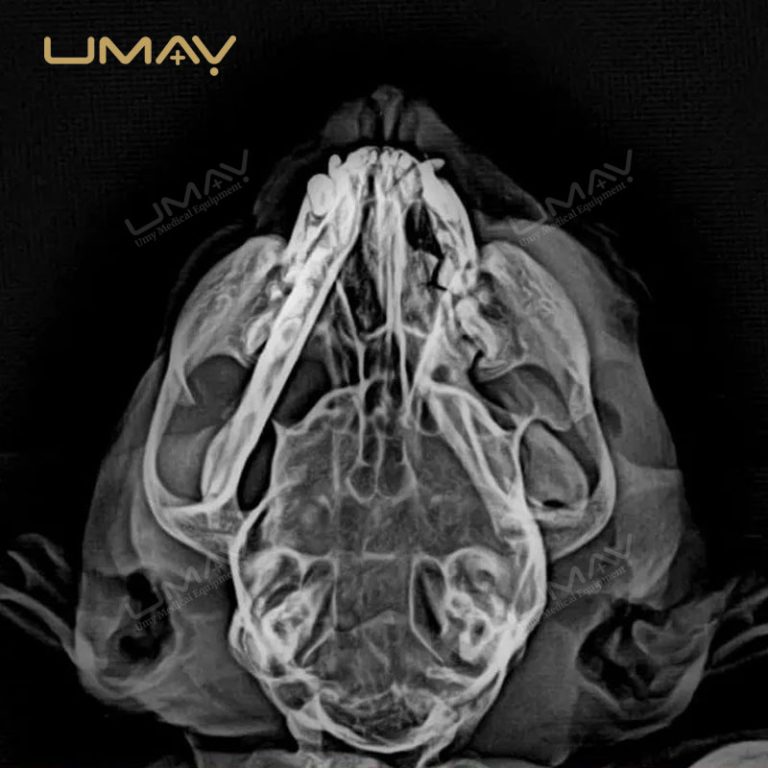

Detector de paneles planos digitales 1417 para radiología de rayos X veterinarios

El detector digital de panel plano 1417 para radiología veterinaria está diseñado para proporcionar imágenes de alta resolución que permiten diagnósticos precisos en una amplia variedad de animales. Su avanzada tecnología DR garantiza una captura rápida y eficiente, reduciendo la exposición a la radiación sin comprometer la calidad de imagen.

Gracias a su diseño ligero y portátil, este detector se integra fácilmente en sistemas de rayos X veterinarios existentes, lo que lo convierte en una opción ideal tanto para clínicas fijas como para servicios móviles. Su versatilidad permite realizar estudios radiológicos en animales pequeños, medianos y grandes, optimizando el flujo de trabajo en entornos de alta demanda.

El panel plano 1417 ofrece una excelente relación señal-ruido y rápida transferencia de imágenes, lo que mejora la eficiencia diagnóstica y reduce los tiempos de espera. Además, su estructura robusta y duradera garantiza un rendimiento confiable incluso en entornos de uso intensivo.

Este detector es una herramienta esencial para clínicas veterinarias modernas que buscan calidad de imagen superior, rapidez operativa y seguridad en los procedimientos, contribuyendo a diagnósticos más precisos y a una mejor atención animal.